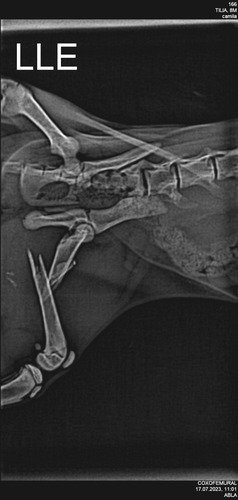

A Otilia é uma gatinha de quase quatro meses que em um dia chegou em casa com a perna com problema. Foi feito exames que constatou a fratura, desde então emagreceu e precisa de ser aliviada rapidamente. Nossa família está juntando para tentar ajudar nos procedimentos que ficarão em torno de R$ 3.140,00. Se vo ê sentir do coração que pode ajudar, qualquer quantia, será muito bem vinda. Desde já agradecemos ♥️🐱